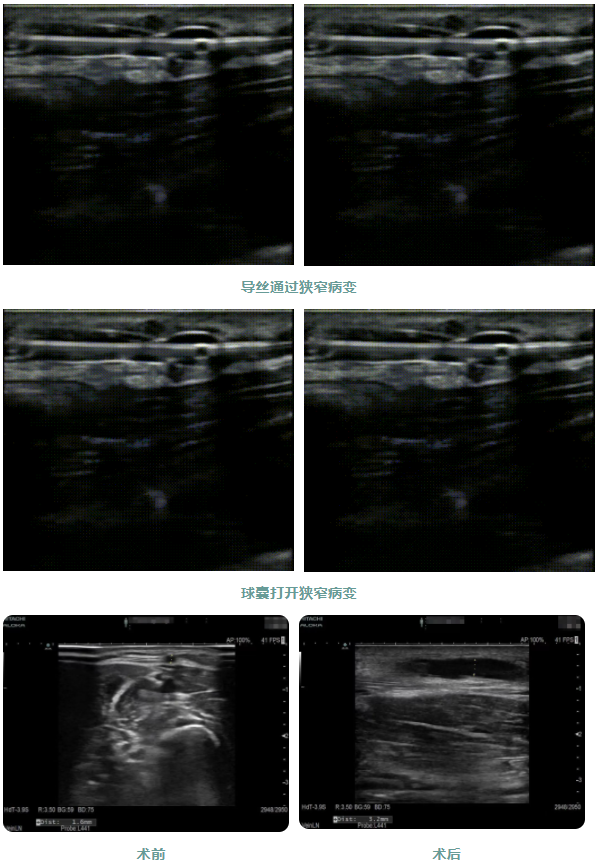

近日,佳木斯大學宏大醫(yī)院腎內科實施超聲引導下動靜脈內瘺球囊擴張術、血栓碎栓術解決內瘺狹窄及血栓,該技術是通過患者皮膚表面穿刺內瘺血管,送入球囊擴張導管,在超聲引導下血栓碎栓后恢復血流,矯正狹窄部位,恢復正常血管內徑,從而延長動靜脈內瘺的使用壽命。

患者1年前出現周身乏力伴有雙下肢水腫癥狀,在外院行“為腎透析的動靜脈造瘺術”后規(guī)律透析治療。因內瘺無震顫2日,為求系統治療來院,入院后腎內科金明花主任帶領醫(yī)護團隊立即完善相關檢查,診斷為:動靜脈內瘺血栓形成,經超聲檢查發(fā)現動靜脈內瘺血栓形成狹窄,最窄處內徑約1.6mm。

為了節(jié)約患者有限的血管資源,盡早治療,經過腎病內科金明花主任及科室共同討論并爭得患者家屬同意后,決定對患者進行超聲引導下動靜脈內瘺球囊擴張術+血栓碎栓術解決內瘺狹窄及血栓。手術過程中金明花主任在內瘺狹窄位置近心端進行穿刺,沿穿刺針置入導絲、置入血管鞘,在超聲實時引導下球囊到達病變部位,緩慢擴張球囊,解決狹窄病變,并壓碎血栓,使內瘺通暢。整個手術僅用30分鐘,用時少,效果明顯,術后內瘺血管雜音及震顫明顯,手術效果立竿見影。